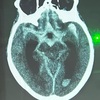

# Neurologia O que representa essa imagem?

Hemorragia subaracnoide. ** delimita o mesencéfalo. forma de coração/mickey.